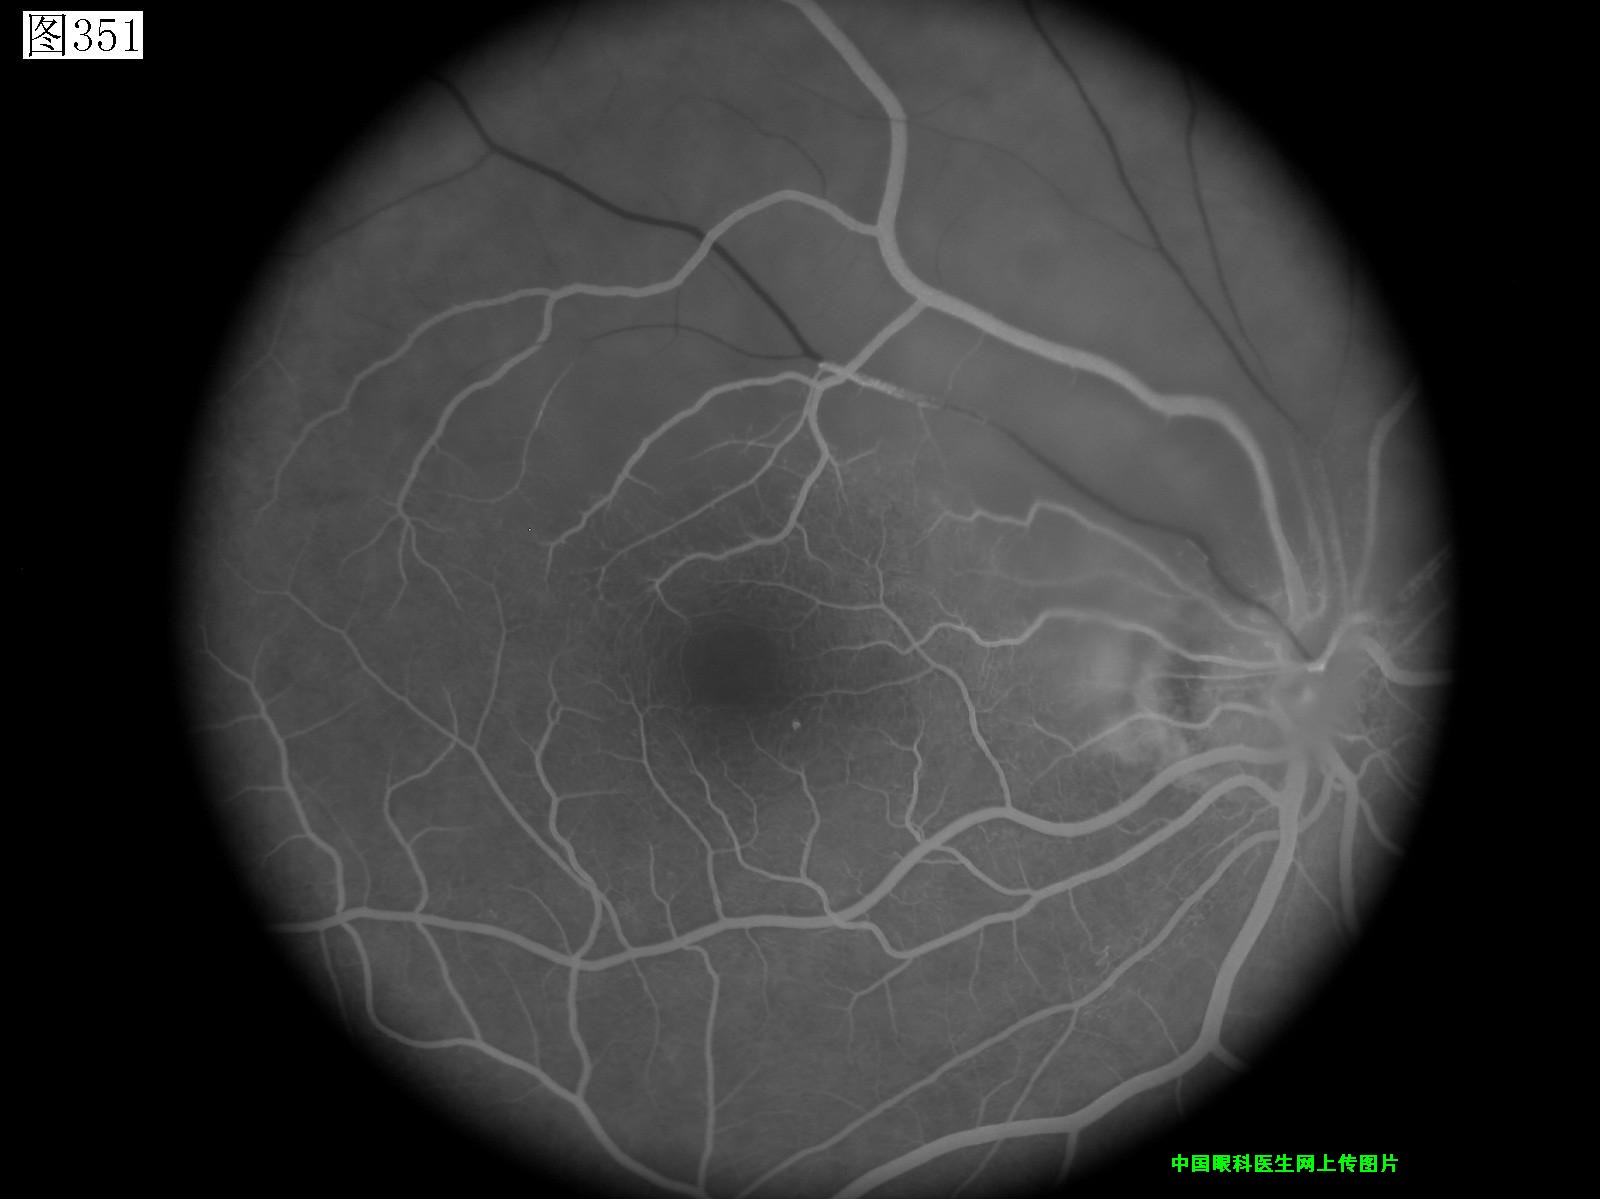

349 350 351 352